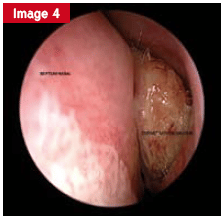

La pathologie croûteuse, moins fréquente, se manifeste par des lésions localisées ou diffuses. Selon l’étendue, des biopsies sont systématiquement réalisées pour rechercher une maladie systémique (sarcoïdose, granulomatose, etc.) ou une cause tumorale. Parfois, l’origine est iatrogène, à la suite d’une intervention chirurgicale excessive ou d’une exposition professionnelle à certains toxiques.

La photo illustre une atteinte croûteuse de la cavité nasale, témoignage de ces formes atypiques.

Après la consultation et l’examen endoscopique, l’association avec l’imagerie permet dans la majorité des situations de cerner la cause. D’autres investigations spécifiques s’ajoutent au besoin. Les pathologies naso-sinusiennes se classent selon leur évolution (aiguë ou chronique), leur extension (localisée ou diffuse), ou selon la bénignité ou la malignité du processus. Au quotidien, la corrélation entre l’aspect endoscopique (œdémateux, purulent, croûteux) et les images radiologiques guide la démarche du spécialiste.